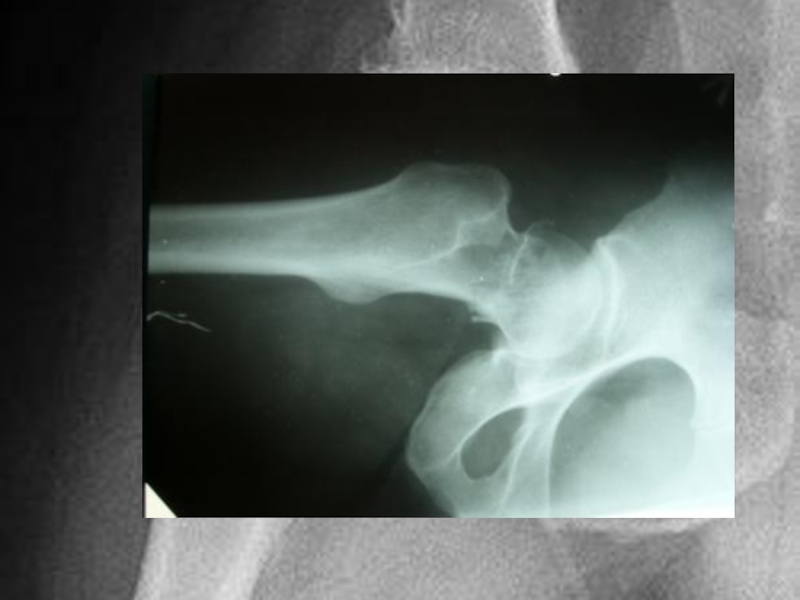

Слайд 14Диагностика

Диагностика при переломах шейки бедра, обычно не составляет труда. Диагноз становится

ясен при клиническом осмотре. Пациент жалуется на боли в области тазобедренного сустава. Поврежденная конечность укорочена, ротирована кнаружи, пациент не может оторвать пятку от кровати. И все это обычно подтверждается при выполнении рентгенограмм.